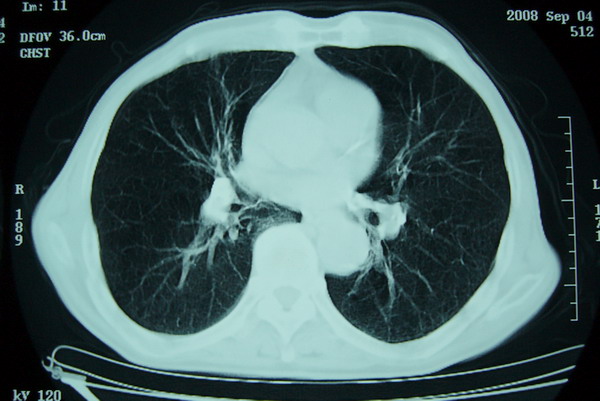

标题: CT15579:男 86岁 咳嗽 咳少量白痰 发热2天 吸烟史60年 [打印本页]

标题: CT15579:男 86岁 咳嗽 咳少量白痰 发热2天 吸烟史60年

右上周围型肺癌,慢支,肺气肿。

分叶及少量边缘性钙化,老年人,周围性肺癌首先考虑。

右肺上叶巨大软组织肿块,轮廓不规则,纵隔内有肿大淋巴结,首先考虑肺癌。

右上肺一不规则团块,边缘有分叶和毛刺,纵隔有淋巴结肿大。右肺周围性肺癌首先考虑。